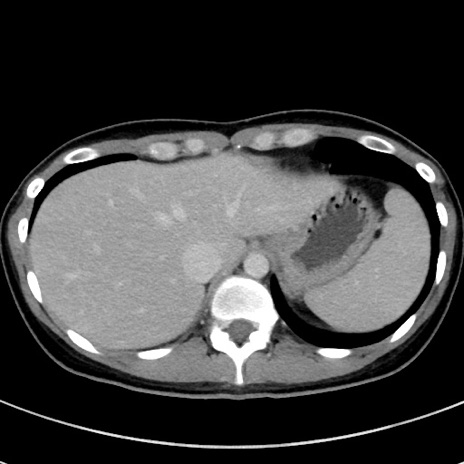

症例17(横断像)

【症例】20歳代女性

【主訴】嘔吐、下腹部痛

【現病歴】昨日夕食後に嘔吐し下腹部痛が出現。本日になっても嘔吐持続し改善しないため来院。

【身体所見】意識清明、BT 37.2℃、BP 108/67mmHg、腹部:平坦、やや硬、下腹部正中から右にかけて圧痛あり、反跳痛軽度あり、tapping pain(+)。

【データ】WBC 13600、CRP 14.94